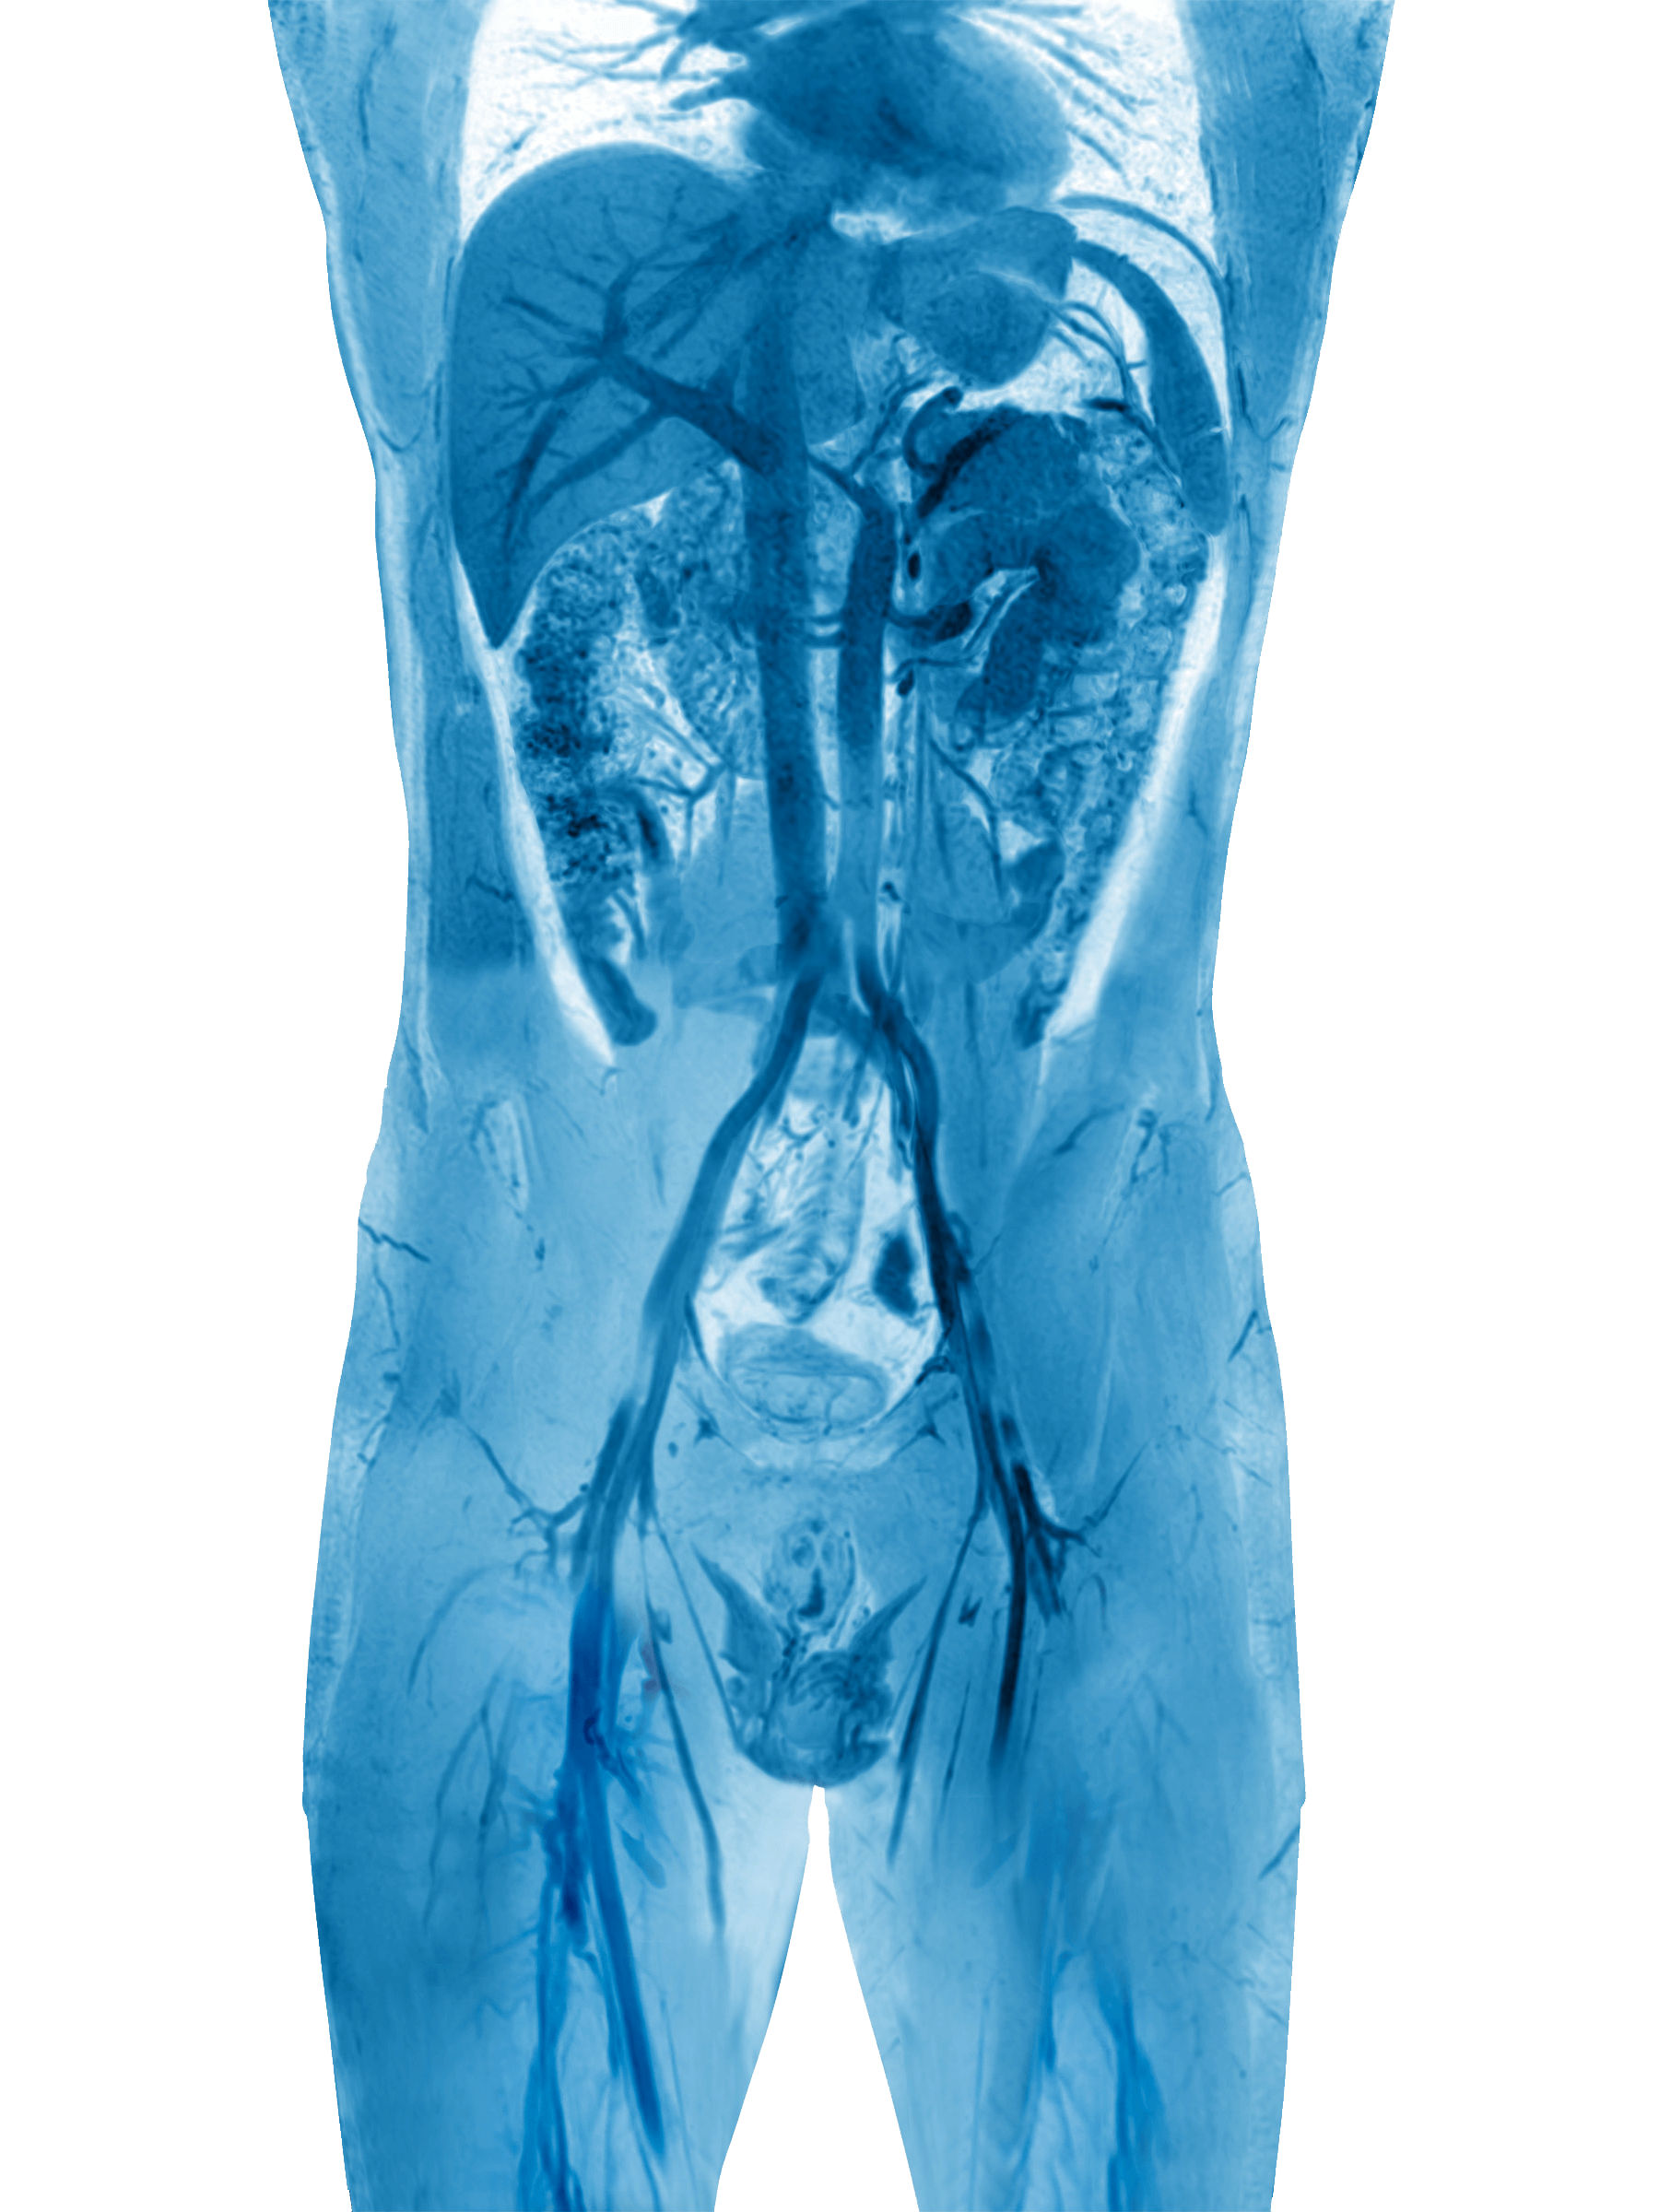

Współczesne badania obrazowe, w tym wykorzystywane na co dzień w Klinice Flebologii badania USG Doppler żył miednicy i jamy brzusznej oraz wenografia rezonansu magnetycznego (MRV), sugerują, że również u panów znaczna część przypadków niewydolności żylnej kończyn dolnych ma charakter wtórny.

Z praktyki zespołu Kliniki Flebologii wynika, iż duże żylaki (śr. > 5 mm) zlokalizowane w worku mosznowym często wynikają z przyczyn, które w rutynowej diagnostyce urologicznej są zwykle pomijane. Z tego względu w diagnostyce rozszerzonej zalecane jest wykonanie badań USG Doppler żył miednicy i jamy brzusznej oraz wenografii metodą rezonansu magnetycznego.

Leczenie żylaków powrózka nasiennego (najczęstszej formy niewydolności żylnej miednicy u mężczyzn) technikami embolizacyjnymi to jedyna małoinwazyjna forma leczenia przyczynowego. Zabieg wykonywany jest z dostępu przezskórnego i przeprowadzany bez konieczności znieczulenia ogólnego.

Leczenie żylaków powrózka nasiennego przez lekarzy Kliniki Flebologii poprzedzone jest zawsze wnikliwą diagnsotyką obrazową (USG Doppler żył miednicy i jamy brzusznej, wenografią MR lub TK oraz flebografią wykonywaną śródzabiegowo).